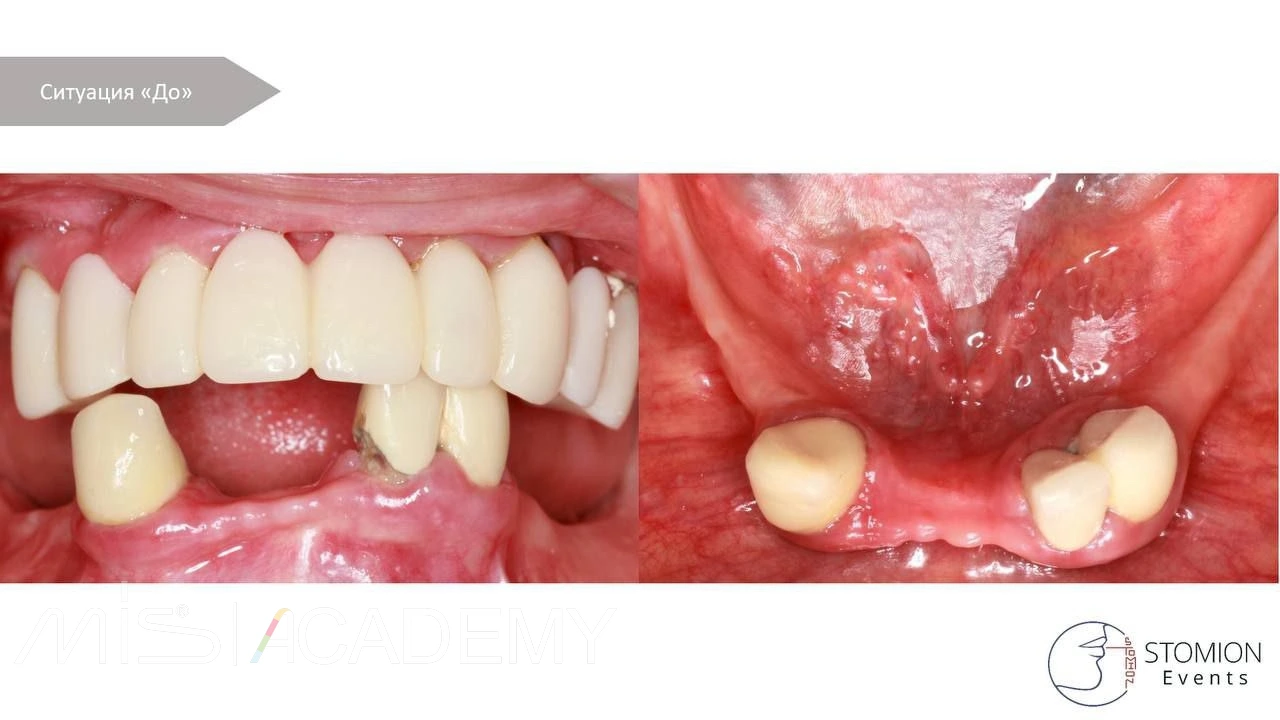

Реферальная работа, выполнена хирургия, передана на протезирование.

В этом посте рассмотрим работу на НЧ.